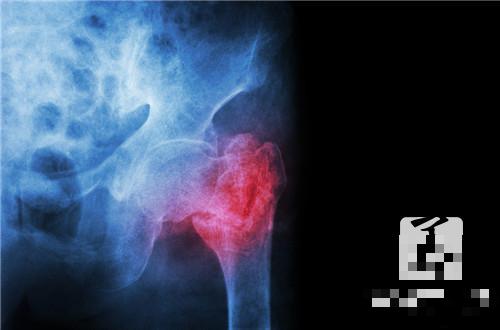

盆腔是女性内生殖器及其周围的结缔组织,盆腔腹膜发生的炎症,炎症可局限于一个部位,也可以几个部位同时发生,可分为急性和慢性两种。女性盆腔范围包括生殖器官(子宫、输卵管、卵巢)、盆腔腹膜和子宫周围的结缔组织。